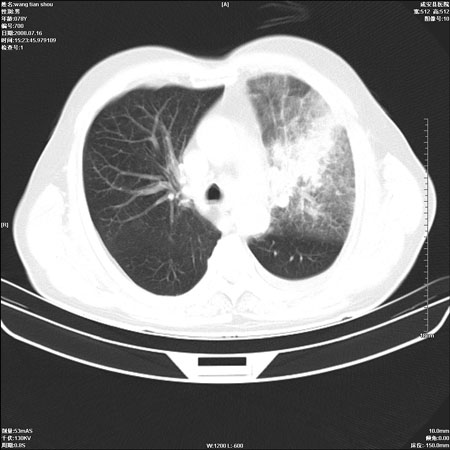

以下是引用qingjing在2008-7-16 19:55:00的发言:[br]1、左上肺不张并堵塞性炎症,建议支气管镜详查;[br]2、左侧胸腔少量积液。

以下是引用wzr在2008-7-16 20:26:00的发言:[br]左肺肺不张伴阻塞性肺炎!另:左侧胸腔少量积液。建议纤支镜检查!